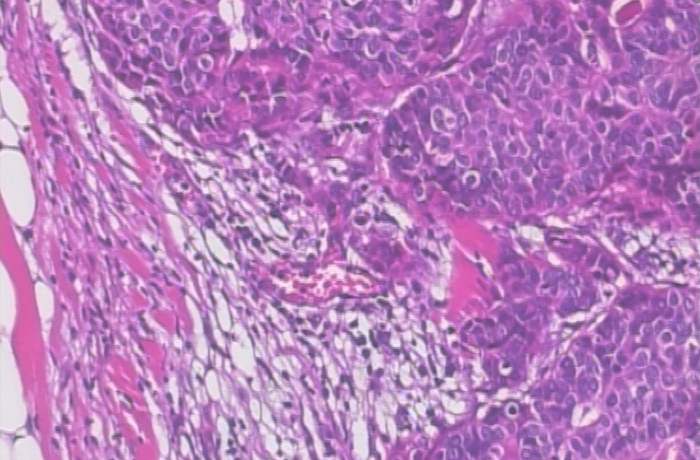

Refer to caption

(a) Malign image sample at 40x magnification.

(b) Malign image sample at 100x magnification.

(c) Malign image sample at 200x magnification.

(d) Malign image sample at 400x magnification.

Figure 2: Representative malign tissue image samples of the BreakHis dataset at different magnifications (40x, 100x, 200x, and 400x) for visual comparison.